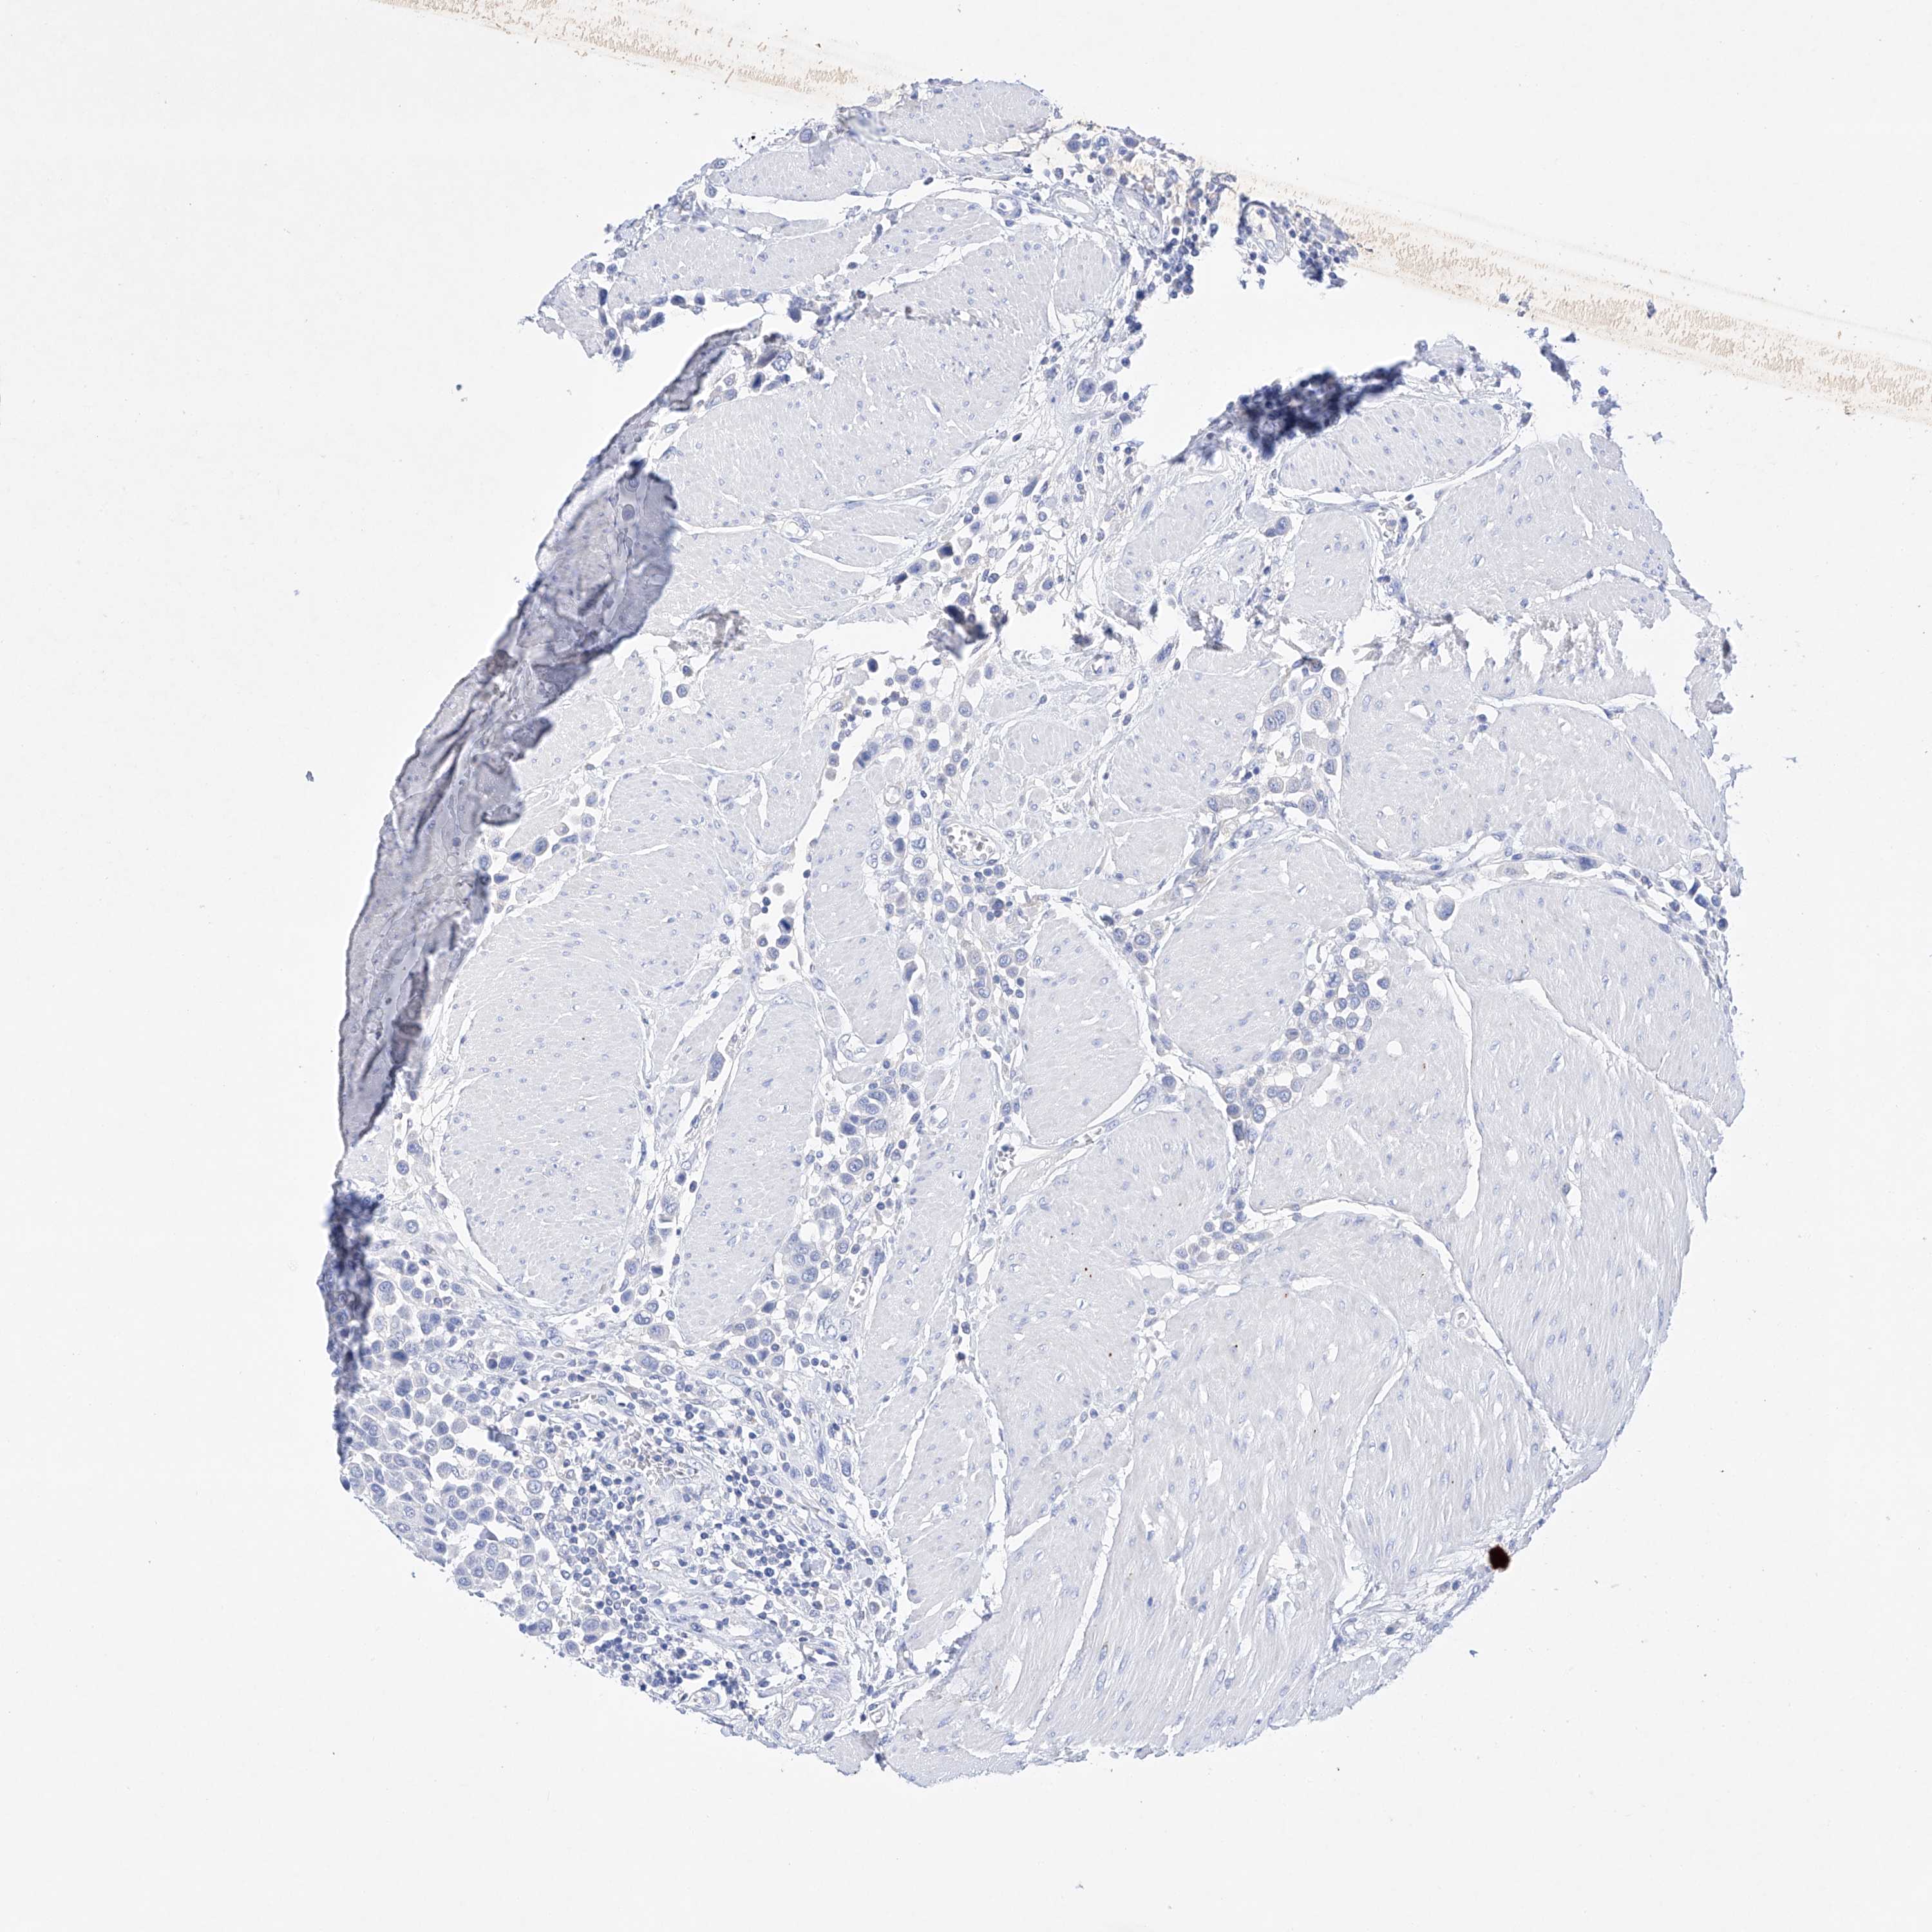

UROTHELIAL CANCER - Protein expressioni

A mouse-over function shows sample information and annotation data. Click on an image to view it in a full screen mode. Samples can be filtered based on level of antibody staining by selecting one or several of the following categories: high, medium, low and not detected. The assay and annotation is described here.

Note that samples used for immunohistochemistry by the Human Protein Atlas do not correspond to samples in the TCGA dataset.

Antibody stainingi

Antibody staining in the annotated cell types in the current human tissue is reported as not detected, low, medium, or high, based on conventional immunohistochemistry profiling in selected tissues. This score is based on the combination of the staining intensity and fraction of stained cells.

Each image is clickable and will lead to virtual microscopy that enables deeper exploration of all samples and also displays staining intensity scores, fraction scores and subcellular localization as well as patient and tissue information for each sample.

Antibody HPA030060

Antibody HPA030061

Urothelial carcinoma, High grade